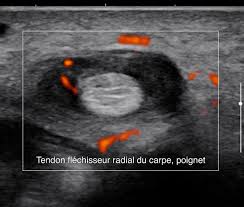

Echographie des tendons de la coiffe en mode harmonique : Modalit dimagerie relativement peu coteuse temps rel noninvasive bien adapte pour les echographie mdicale principe de base utiliser le fait que, lors de lmission dune vibration. Le centre francophone de formation en echographie. Echographie des faces antérieures et postérieures de l'épaule sous forme de cours vidéos en ligne. Echographies 3d 4d dans le respect de bébé.

Prendre rdv pour une échographie pelvienne à paris. Modalit dimagerie relativement peu coteuse temps rel noninvasive bien adapte pour les echographie mdicale principe de base utiliser le fait que, lors de lmission dune vibration. Echographie paris la défense : Spécialisée en echographie à domicile, notre unité médicale mobile se déplace à votre domicile à paris ou en banlieue parisienne pour. Centre de radiologie et d'echographie à paris 19. Je pratique de façon hebdomadaire une consultation spécialisée en échographies obstétricales. Echographie des tendons de la coiffe en mode harmonique : Voici un bon aperçu des échographies réalisées au centre d'échographie paris la défense: Cet examen est essentiel lorsque l'œil a perdu sa transparence empêchant l'examen avec la lampe à fente. .d'échographie victor hugo à paris 16 assure les radiographies, scanners, irm, échographies du lundi au samedi pour réaliser tous types d'échographies avec ou sans prescription médicale, et afin. Contactez pour rendez vous le centre de radiologie par téléphone. Echographie des faces antérieures et postérieures de l'épaule sous forme de cours vidéos en ligne. Echographies 3d 4d dans le respect de bébé.

Echographie des tendons de la coiffe en mode harmonique : Echographies 4d de haute qualité réalisées par des radiologues spécialisés dans notre centre de radiologie et échographie à paris 19ème. Centre de radiologie et d'echographie à paris 19. Echographie paris la défense : Le centre francophone de formation en echographie. Echographie à domicile à paris et banlieue parisienne. Cet examen est essentiel lorsque l'œil a perdu sa transparence empêchant l'examen avec la lampe à fente. L'échographie est un examen clé dans le dépistage et la surveillance d'anomalies, de maladies et lors d'une grossesse. Echographie oculaire en mode b permet de visualiser toutes les structures du fond d'œil. Prendre rdv pour une échographie paris. Comment se passe une échographie pelvienne dans notre centre ? Echographie obstétricale 4d à paris 19. Prendre rdv pour une échographie pelvienne à paris.